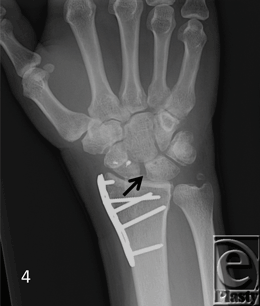

The patient demographics, clinical findings, X-ray, and 4D CT imaging findings as well as final patient disposition are depicted in Table 1. All subjects were successfully scanned in various wrist motions (Patient 1-4 videos). 4D CT image quality was adequate in all subjects, and carpal kinematic behavior was easily assessed in various wrist motions both before and after surgical repair. The normal postoperative (Patient 1-3 videos) and altered carpal kinematic behaviors (Patient 4 videos) correlated well with the clinical findings. In the operated wrists (Figs 2-4), while X-rays demonstrated slight gaping after scapholunate ligament repair, kinematic imaging demonstrated no abnormal widening with dynamic motion and showed normal dorsally hinged scissoring type scapholunate motion with motion. However, normal mid-carpal initiated wrist motion on flexion/extension was replaced by radiocarpal initiated motion, likely because of midcarpal stiffness/scarring. Clinical suspicion of ulnocarpal abutment was also confirmed in both wrists of Patient 4 (Fig 5).

Patients with obvious findings necessitating surgical intervention such as the radiographic findings already mentioned, or more complex injuries such as a perilunate or lunate dislocation, may have questionable radiographic findings even after surgical repair/reconstruction. A persistent 3- to 4-mm scapholunate gap suggesting persistent ligamentous instability despite repair on multiple unchanging postoperative X-rays following fixation removal can be common finding that delays initiation of wrist motion rehabilitation and return to normal function, as it was observed in patients 1 to 3. For these reasons, we have begun incorporating Dynamic 4D CT imaging into our postoperative imaging following commencement of wrist motion and rehabilitation for patients with interosseus ligament injuries of the wrist. We could obtain good diagnostic quality imaging and 4D reconstructions in all subjects without significant beam hardening artifacts similar to earlier results on 256-row detector study.34 For this modality to have its highest diagnostic sensitivity and specificity, it requires a thorough knowledge of wrist kinetics to appropriately appreciate what motion is normal and what motion is abnormal. This requires collaboration of hand surgeons and radiologists with study of normal dynamic studies and comparison with abnormal studies. These cases represent our early experience with this modality and how it has assisted in appreciating the postinjury wrist motion as well as helped guide activity and treatment postoperatively.